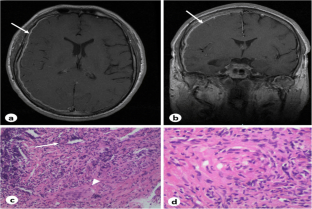

Fig. 2